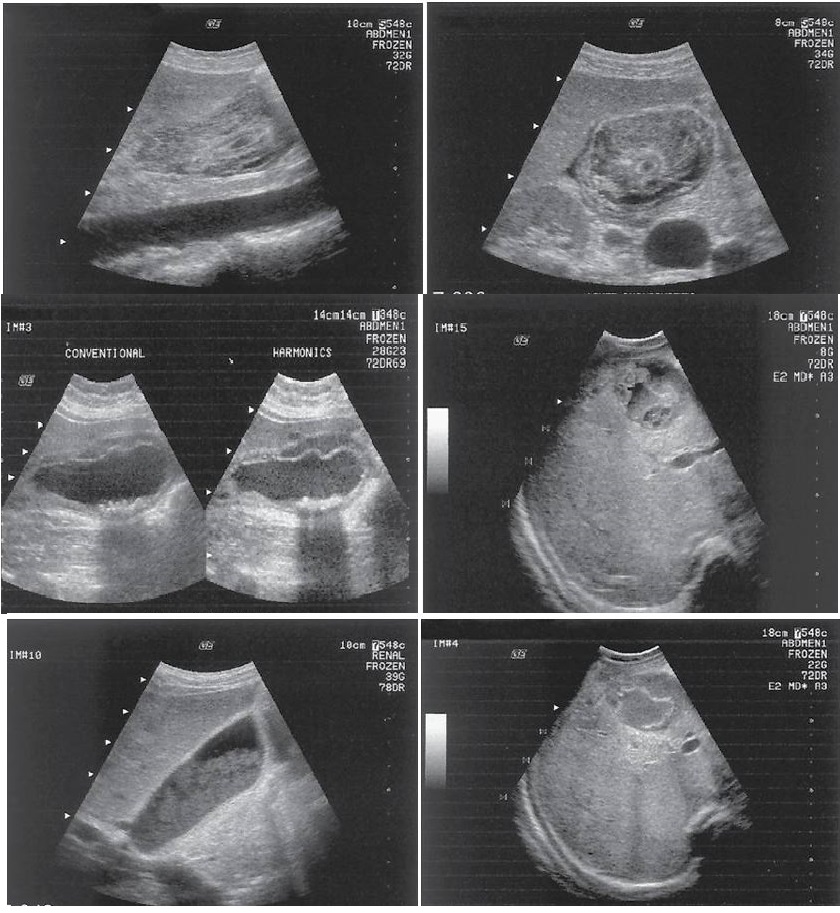

different patterns of cholelithiasis

what is this showing

Cholelithiasis w Floating Stones

Cholelithiasis showing multiple small floating and

nonfloating gallstones

Wall Echo Shadow “WES” Sign